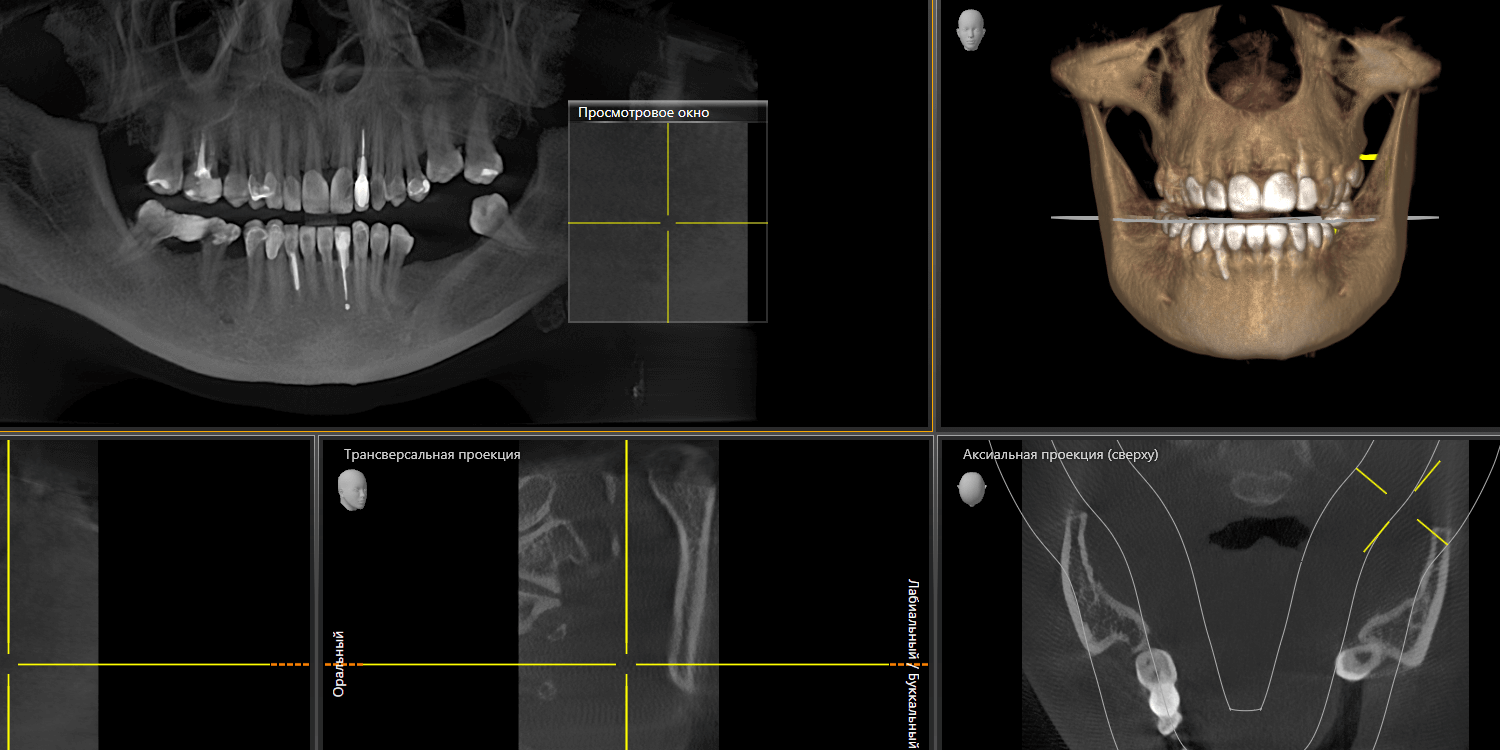

Впервые мы встретились с пациенткой примерно год назад. Тогда она обратилась к нам в клинику для проведения профессиональной гигиены полости рта и были жалобы на отсутствие зубов 6 и 7 на нижней челюсти слева. После КТ-исследования и осмотра обнаружили, что некоторые зубы (ранее протезировавшиеся) уже депульпированы. Практически все зубы были покрыты коронками, полукоронками и винирами. Относительно старые, но в удовлетворительном состоянии. Объем костной ткани позволял провести имплантацию зубов. Предложили установить зубные импланты методом двухэтапной имплантации на место отсутствующих зубов с дальнейшим протезированием цельнокерамическими коронками.